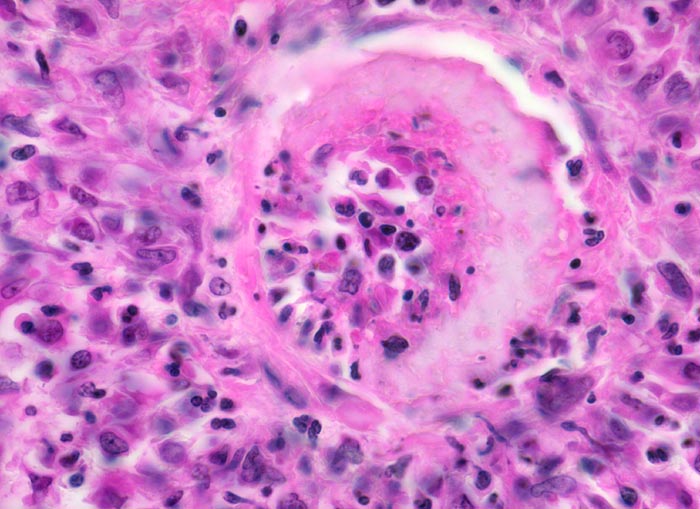

Aktive Vaskulitis: Infiltration und/oder Destruktion der Gefässwand durch ein Entzündungsinfiltrat. Intraluminale Fibrinthromben oder intramurale Fibrinablagerungen (fibrinoide Nekrose).

In den beteiligten Organen sind nicht alle Arterien pathologisch verändert und oft ist die Gefässwand nicht zirkulär sondern nur segmental betroffen und die Gefässveränderungen befinden sich in unterschiedlichen Stadien. Folgen der Gefässveränderungen sind Infarkte und Mikroaneurysmata. Die Nieren sind im akuten Stadium oft vergrössert. An der Oberfläche sind Petechien neben unterschiedlich grossen Infarkten erkennbar. Gelegentlich erkennt man auf der Schnittfläche Gefässaneurysmata, thrombosierte Arterien und Papillennekrosen. Im häufigeren chronischen Stadium sind die Nieren verkleinert und aufgrund von Infarktnarben grob gebuckelt.

Befallen sind prärenale und grössere intrarenale Nierenarterienäste bei meist fehlender Beteiligung der Arteriolen und definitionsgemäss fehlendem Befall der glomerulären Kapillaren. Die betroffenen Gefässe zeigen segmentale transmurale oft durch Thrombosierung komplizierte Wandnekrosen mit initial granulozytenreichem Infiltrat. Im Verlauf werden die Nekrosen durch Granulations- und Narbengewebe organisiert. An grossen Arterien kann dies zu Knotenbildungen und Aneurysmata führen. Oft findet man in ein und demselben Gefäss frische Nekrosen neben reparativen Veränderungen und Narben. Das übrige Nierengewebe zeigt als Folge der Vaskulitis Kollapsglomerula, Infarkte und ischämische Tubulusatrophie mit begleitender interstitieller Fibrose und Entzündung.